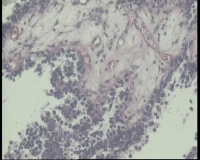

| 一般病史 | 彩超:盆腔可见囊实性回声,囊性为主,大小约5.0x3.7厘米,其内可见分隔回声,部分分隔内回声不纯净,形态欠规整 | ||||

| 标本名称 | 腔镜下右侧卵巢囊肿手术 | ||||

| 大体所见 | 囊壁样组织5.5x5.0厘米,4.5x2.5厘米2块,壁厚0.1-0.2lm,囊壁大部分光滑,局灶见0.7x0.5x0.3厘米淡黄色突起组织,另见淡黄色、肉粉色质软组织2.8厘米一堆。 | ||||